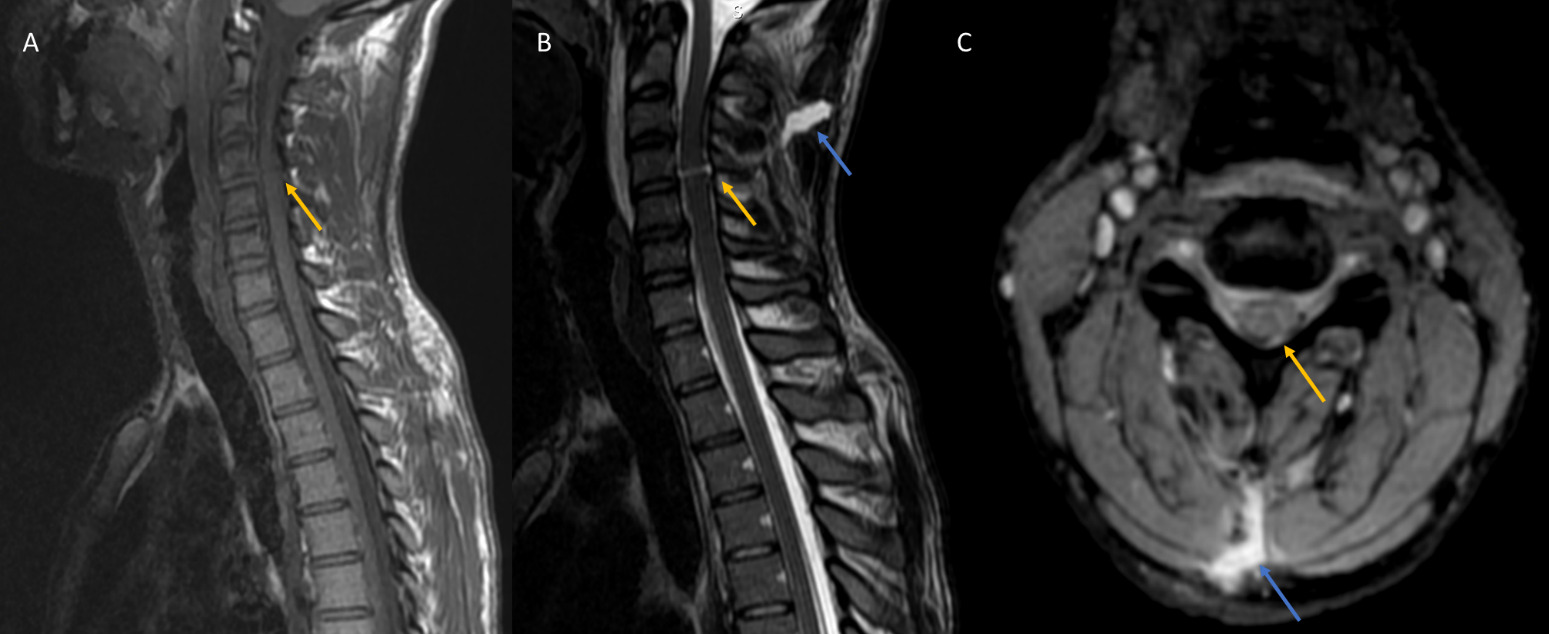

A spine MRI was performed, showing a disruption of the interspinous ligaments between C4 and C5, with a linear band in the spinal cord, hypointense signal on T1 and hyperintense signal on T2, corresponding to a complete transection of the cervical spinal cord at the level of C4, explaining the quadriplegia and the absence of breathing abnormalities. The continuity of the T2 hyperintense signal in the midline soft tissue corresponds to the knife tract (Figure 1).